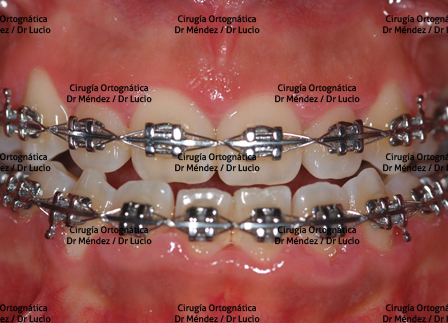

RETROGNASIA E HIPOPLASIA DEL MENTÓN Paciente operado de avance de mandíbula y mentoplastia de avance |

||